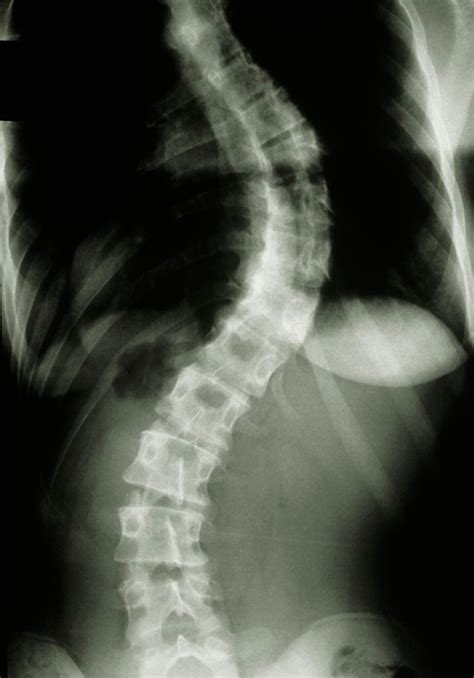

Better Imaging Will Enhance Every Future Scoliosis Srs

SRS | Scoliosis Research Society